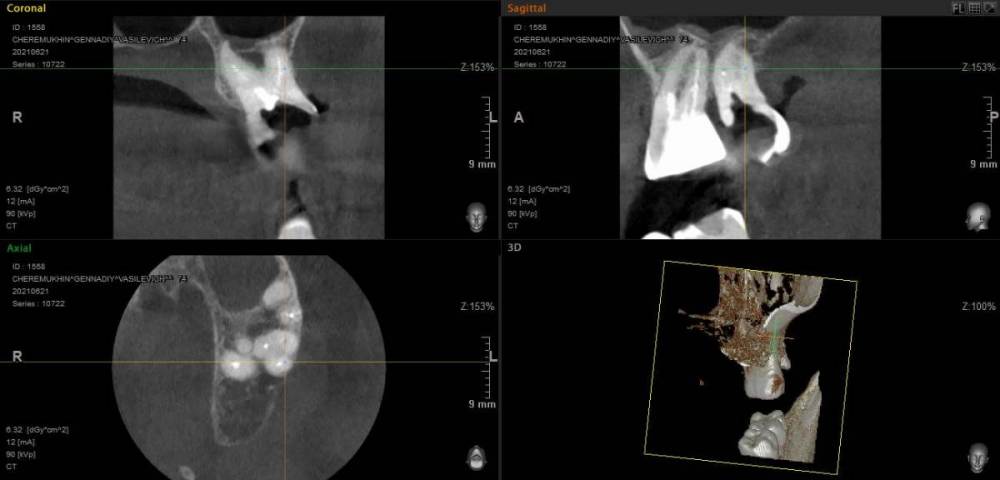

GENRY Опубликовано 6 сентября, 2021 Поделиться Опубликовано 6 сентября, 2021 Здравствуйте! Как лучше восстановить ( пусть частично) 28 зуб? Удаление не желательно т.к. с имплантацией связываться не хочу (синус лифтинг.. возраст 75 лет...) ,а опор для ортопедических конструкций нет. Кроме того боюсь, что в процессе удаления будет разрушена пломба 27 _го. Оптимизма добавляет история 27 го На орто 2012г показан 27 до его восстановления и до вмешательства в 28 зуб с добавлением в него пломбы в 2012г . Канал 28_го (небный ?) был уже запломбирован кем то раньше, скорее всего резорцин-формалиновой пастой) Доктор в 27 - м обнаружил на снимках 3 канала, наполовину прошел небный и полностью прошел дистально- щечный канал с наполнением их горячей гуттаперчей . Поскольку устье 3_го канала обнаружено не было, восстановил 27 зуб 2_мя стекловолоконными штифтами с использованием Build-It . Дистальную стенку сделал, кажется на основе пасты СПЕКТРУМ . К дальнейшей судьбе 27_го доктор отнесся скептически ( не более 2_х лет!), но похоже сработал надежно, пошел уже 10_й год, а 27 все стоит. Но 10 мес. назад выпала пломба 28 _го и он принял вид показанный на снимке. Не беспокоит. Хотелось бы повторить историю с 27_м, т.е. восстановить 28 по типу 27_го .... думаю мне хватит 5_7 лет... Регулировать нагрузки на этой стороне челюсти я научился. Сделал КТ сегмента 27_28 (В Пикассо, Vatech, просмотрщик EZ3D2009 plus ) но не смог найти ( сейчас живу в Феодосии ) терапевта работающего с этой программой. Кто то вообще не использует никакие КТ (но при этом берется за восстановление штифтом без перелечивания каналов) , кто то готов к перелечиванию, но полагается только на свои мануальные навыки, игнорируя КТ или формально глянув на пару проекций. На последней консультации добился 4-х снимков из КТ, но в общем то случайных и скорее всего не показательных.. Выкладываю скриншоты... Понял, что надо выходить за пределы городка и расширять собственное (к сожалению) понимание возможных вариантов лечения и их последствий. Вопросы по 28: 1. Если хотя бы один канал запломбирован (видимый на снимке) то это автоматически означает вскрытие камеры , а значит вскрытие и убитость содержимого (нервов, сосудов) всех остальных каналов , поскольку их устья на дне камеры? (Да, Нет, Другое) 2. Если Да, то нормально ли было пломбировать 28, не найдя и не залечив (с пломбировкой) другие каналы одновременно с небным (я имею ввиду сейчас самую раннюю пломбировку, до представленного орто) 3. Поскольку пломбировки всех каналов (сколько их ?) точно не было, то за эти 10-15 (?) лет (уже сейчас зуб стоит открытым почти год (ковид, консультации..)) должен развится пульпит, периодонтит... ? Или не обязательно? Ничего не болело, никаких выделений не было 4. Есть ли признаки какой либо хроники, воспалений в тканях на снимках? 5. Если ткани зуба и около него в порядке, то может не обязательно перелечивать все каналы, чтобы не ослаблять зуб? А только те, в которые будут вставлены штифты? Вкладка, похоже исключается т.к. феррул не замкнут на стыке с 27 зубом. 6. Есть ли какие либо оценки минимального количества требуемых штифтов ? 7 . Поскольку за 4 консультации я так и не получил ответов и снимков срезов (по КТ )показывающих количество и топологию корней и каналов, то придется добывать эту информацию самому. Буду благодарен за ссылки на материалы показывающих как это делается т.е. в каких из 3 проекций, при каком положении осей и.т.п. Я нашел только хороший ролик Ервандяна А.Г., но мне недостаточно, не хватает знания топологии зубов. Спасибо за внимание. Ссылка на комментарий